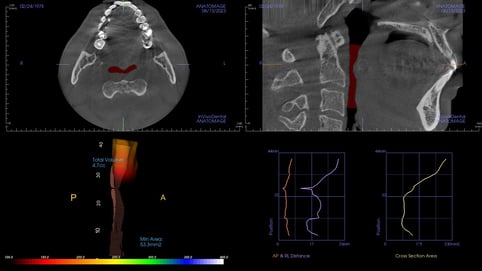

術前評估

- 下顎位置偏後,口咽空間受限

- AHI:24.9(中度阻塞型睡眠呼吸中止症)